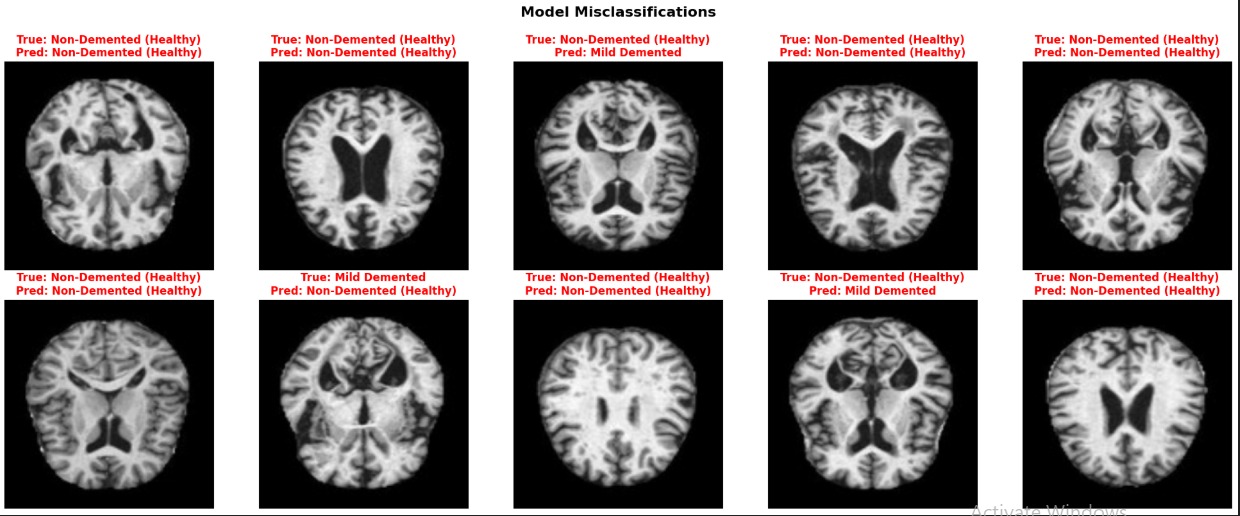

BrainGuard classifies brain MRI scans into four categories:

Glioma (brain tumor) Meningioma (tumor) Healthy (no disease) Pituitary (tumor)

It provides fast classification (< 1 second) with visual explanations using Grad-CAM to show which brain regions influenced the decision.

Class Imbalance: Initial model just predicted "Healthy" → Fixed with weighted loss Slow Training: 6+ hours on CPU → Switched to Google Colab GPU (2 min/epoch) Reproducibility: Different results each run → Set random seeds everywhere Grad-CAM Compatibility: API changes broke code → Updated to latest documentation